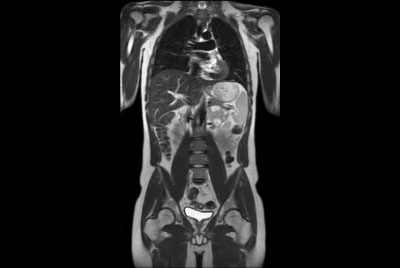

Abdomen large FOV imaging